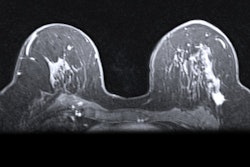

A group of Russian scientists has proposed a device that can be used to update existing MRI scanners, allowing for breast MRI to be conducted using standard scanners without specialized radiofrequency receive coils. Image courtesy of Nature Communications.Rather than generating or receiving the signal, the device only focuses the magnetic field in a specific place and then transmits the energy of excited protons to the large coil, according to the researchers. As the electromagnetic field is now concentrated inside the area of the interest, the body coil's power can be turned down, enabling the MR examination to become safer for patients, the authors noted.